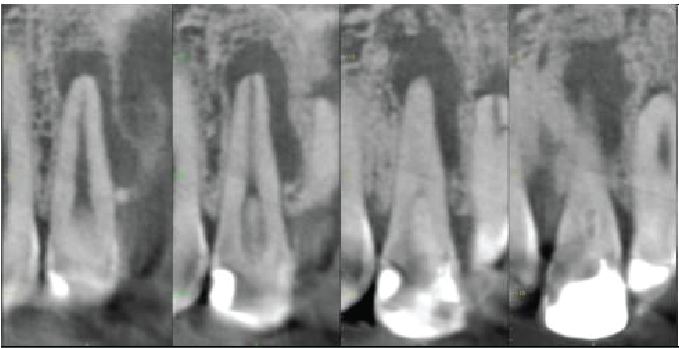

Cross sectional images of UL2

Mesio-distal

Labio-palatal

Oblique (mesio-labial to distopalatal) to show lateral canal

The UL2 has a heavily restored crown. Dens invaginatus anomaly seen (Oehler type I). The root canal is patent. Projections of the root canal pass mesially and distally around the deep part of the invagination and presumably meet on the palatal side. There is also a lateral canal 2.5mm from the apex directed mesiolabially. There is a 7.5mm maximum diameter periapical radiolucency, extending along the mesial side of the root almost to the crestal bone level. The apex is flattened, indicating some apical inflammatory resorption.